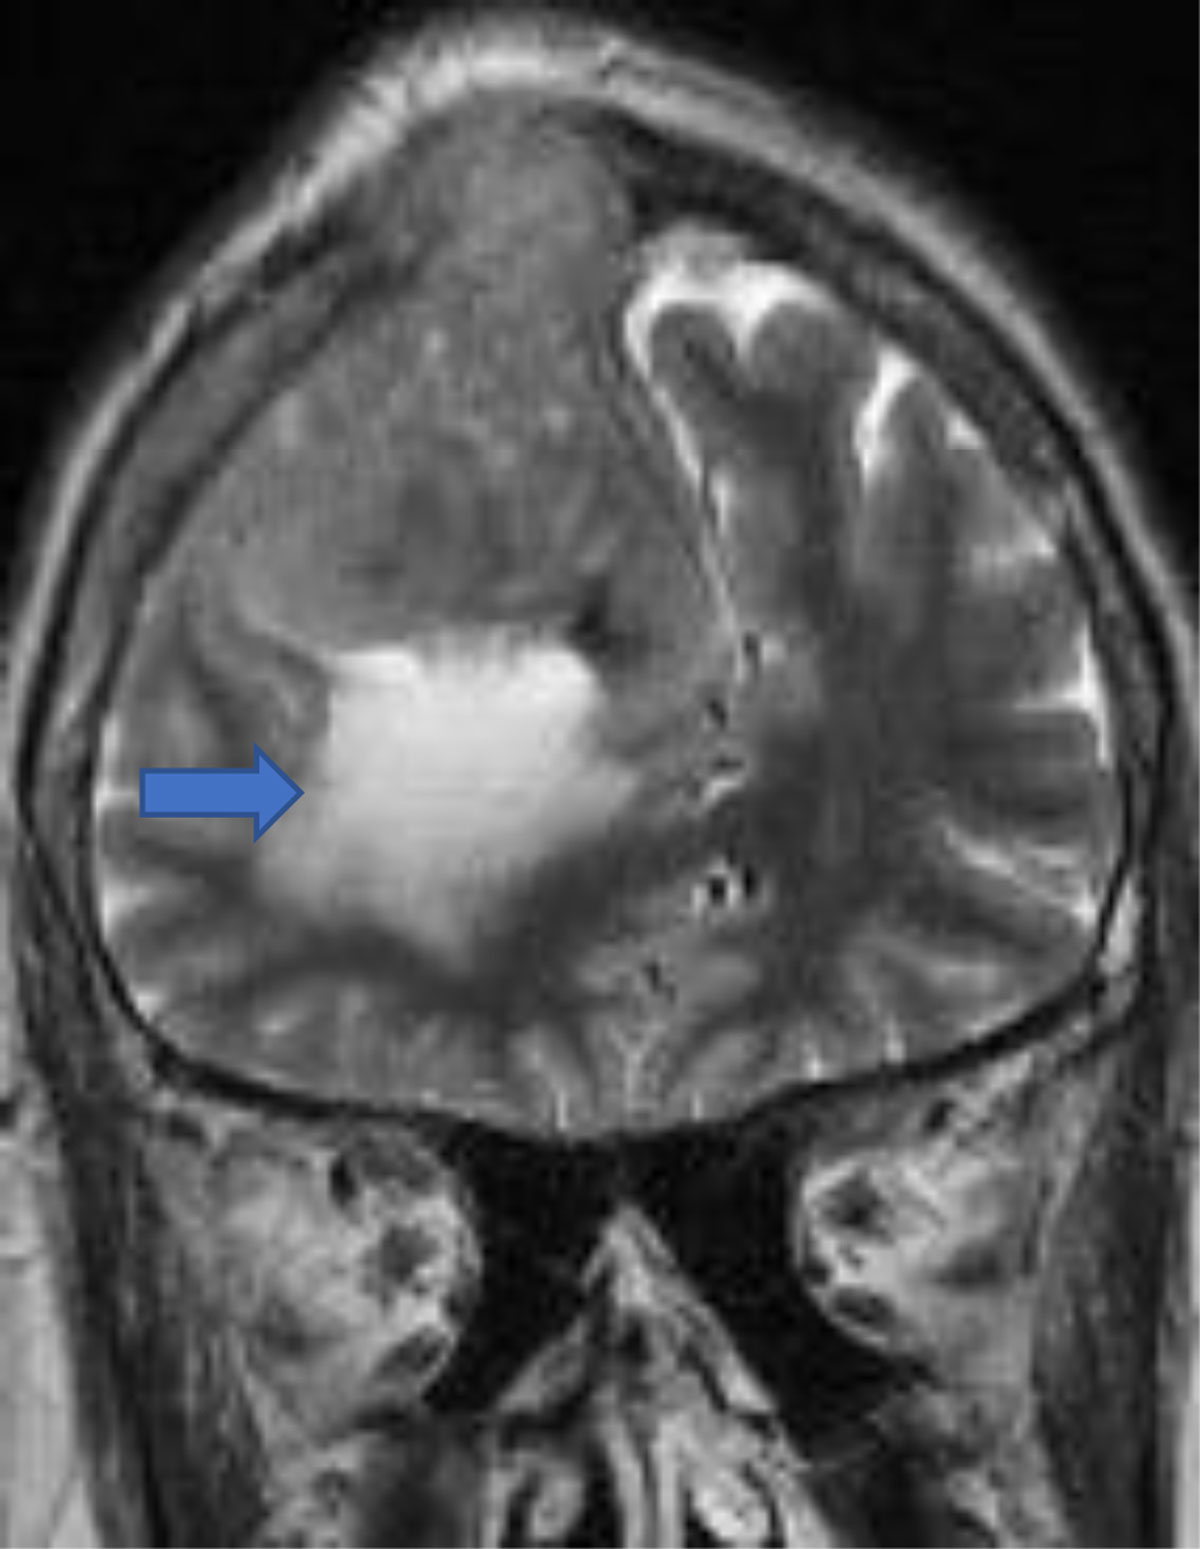

Peritumoral edema is seen in almost 50% of lesions. It is related to pial blood supply and vascular endothelial growth factor (VEGF) [16]. Infiltrative and microcytic meningiomas are associated with significant edema [7] (Figure 9).

Figure 9

Convexity meningioma with peritumoral edema and (arrow) osseus invasion.